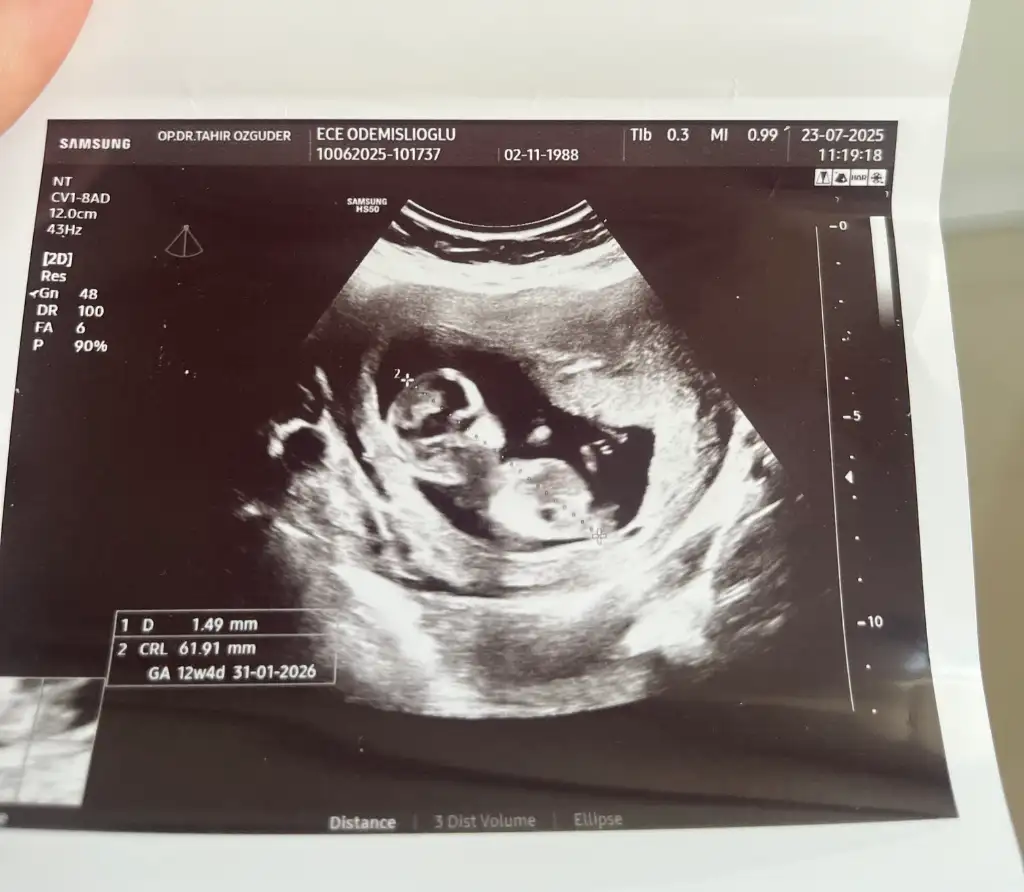

Günaydın canım. Allah bağışlasın. Kız gibi geldi banaBenimde bakarmısınıs 9haftalık gebelik

Dun doktora gitimde erkeye benziyor dedi inşallah allah gonlumuze gore verirGünaydın canım. Allah bağışlasın. Kız gibi geldi bana

Merhaba benim de yorum yapar mısınızGünaydın canım. Allah bağışlasın. Kız gibi geldi bana

Kız gibi duruyor canım. Allah bağışlasınMerhaba benim de yorum yapar mısınız